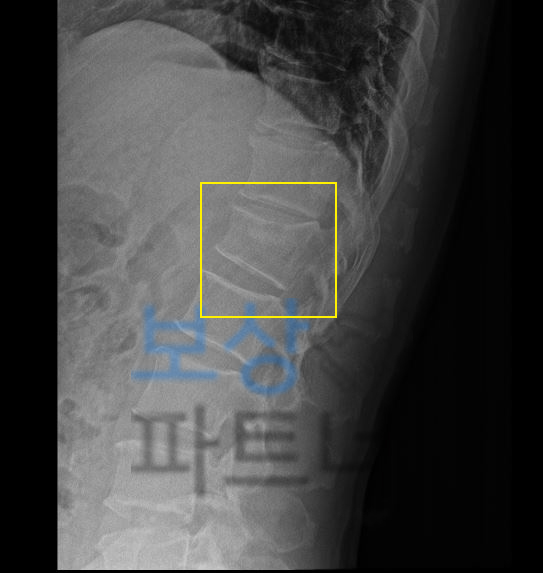

흔히 척추 1번 이라고 생각하시는 요추의 1번 골절 진단 받으셨습니다. 특히 요추1번 부위는 척추 골절 시 가장 빈번하게 발생하는 부위 중 하나인데요, 본래 자연스러운 S만곡을 형성하는 척추의 흉추와 요추가 교차하는 부위로서 추락사고, 낙상사고, 미끄러짐 사고에 금이가고 골절되는 사고가 많이 일어납니다.

요추1번 골절된 김@@님은 다행히 골밀도도 나쁘지 않아 보존적 치료로 TLSO 보조기 착용하며 3개월 정도 침상안정을 취하셔야 했는데요, 이러한 상황에 내가 가입해둔 보험에서 내가 가입한 보험에서 후유장해 항목 찾아보세요!